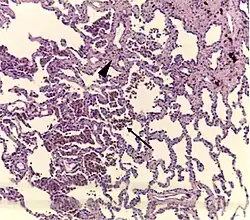

A "smoker's macrophage", with yellow to light brown and finely granular cytoplasmic pigment. | |

Respiratory bronchiolitis is a lung disease associated with tobacco smoking.[1] In pathology, it is defined by the presence of "smoker's macrophages".[1] When manifesting significant clinical symptoms it is referred to as respiratory bronchiolitis interstitial lung disease (RB-ILD).[1]

- Pathologic: Lung biopsy with "smoker's macrophages" limited to distal airspaces and peribronchiolar airspaces, and minimal to absent peribronchiolar interstitial fibrotic thickening